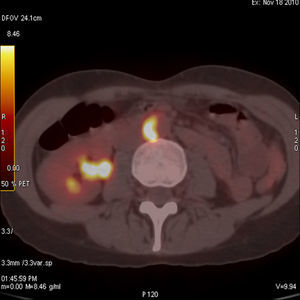

Caso clínico 1Mujer de 43 años con antecedentes de sinusitis crónica, úlceras corneales y blefaritis de repetición, en tratamiento con 30mg de prednisona al día tras haber sido estudiada en la unidad de enfermedades infecciosas por febrícula vespertina persistente de 37,5°C, donde se descartó origen microbiológico. Pasadas unas semanas de mejoría clínica ingresa en reumatología por fiebre de hasta 39°C de 15 días de evolución, que cedía con antipiréticos, cifras de tensión arterial (TA) de 100/60mmHg y parestesias en pie izquierdo, por lo que se realizó un estudio neurofisiológico que demostró un patrón electroneurográfico de bloqueo de la conducción a nivel distal del tibial posterior izquierdo, compatible con la vasculitis del sistema nervioso periférico. En la analítica destacaba una discreta leucocitosis con mínima desviación a la izquierda, velocidad de sedimentación globular (VSG) de 97mm (valores normales hasta 25mm) y proteína C reactiva (PCR) de 1,22mg/dl (normal hasta 0,5mg/dl) siendo el estudio de autoanticuerpos -incluyendo los anticitoplasma (ANCAS)-, negativo. Se realizó estudio de líquido cefalorraquídeo que mostró pleocitosis leve constituida por linfocitos. La primera sospecha clínica fue de poliarteritis nodosa (PAN), por lo que se decidió realizar una biopsia muscular y del nervio sural que resultó inespecífica. Por su antecedente de sinusitis se pensó en una poliangitis con granulomatosis o granulomatosis de Wegener (GW), por lo que se solicitó una biopsia de mucosa afectada que la descartó. En todo momento los pulsos periféricos permanecieron presentes y simétricos, sin diferencias significativas de la TA entre ambos brazos, no se detectaron soplos a la auscultación de aorta ni subclavias y la paciente no refería clínica de fatiga o malestar muscular con los movimientos que sugiriese claudicación. A los 10 días de ingreso comienza con cefalea occipital y frontal con fotofobia resistente a tratamiento analgésico y crisis hipertensivas (160/95mmHg) que cedían con la administración de IECA. Manteniendo nuestra sospecha clínica de vasculitis realizamos una angiorresonancia magnética (ARM) de aorta (Ao) −que no mostró alteraciones−, una RMN cerebral donde se comprobó la existencia de paquimeningitis y un TAC toracoabdominal que mostró un pequeño aneurisma infrarrenal de 2cm de diámetro. Por último, se realizó un PET-TAC que mostró lesiones hipermetabólicas en cono y bifurcación pulmonar, así como en la pared de la Ao abdominal (fig. 1), que junto con el sexo, la edad, la afectación de vasos de gran tamaño (Ao y pulmonar), la presencia de aneurismas, la negatividad de los ANCAS y la exclusión mediante biopsia de PAN y GW, hacen muy probable el diagnóstico de enfermedad de Takayasu (ET) ante la dificultad de realizar biopsia de la zona afectada.